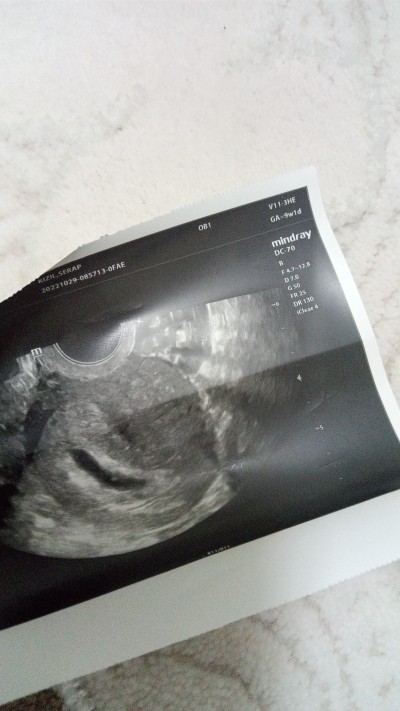

Merhaba 8 haftalık gebeyim bugün doktora gittim fakat kese büyümüş içinde bişey var diyor geri diyor sonra diyor yok bebek de kalp atımı da duyulmadı doktor 1 hafta sonra gelin yine gorunmezse boş gebelik dedi zaten en başından beri bize geç döllenme dedi haftasını geriden takip ediyor dedi

image

Sizce orada bişey görünüyor mu ben görüyorum ama minicik bı karartı

Evet var orda bişey kuzum içini ferah tut canı veren Allah geç döllenme oldugu için böyledir adetin kaç gün geçtikten sonra öğrendin canım hamile oldugunu kaçla öğrendin

Minicik beyaz nokta gibi bişey var sanki ya banami öyle Geldi biraz daha bekle canım ❤️